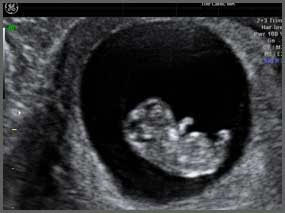

Baby scan image 2